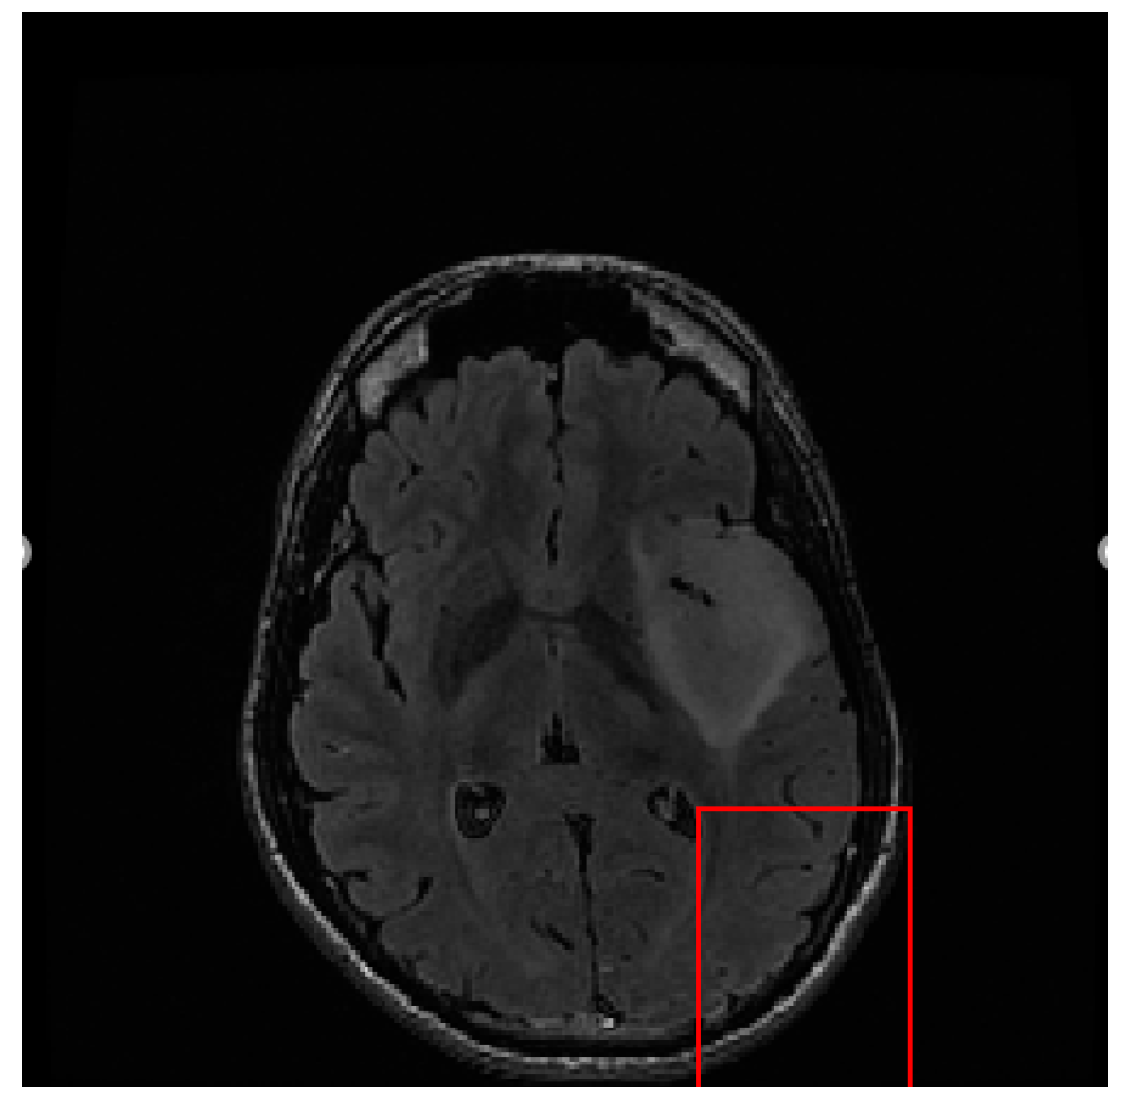

Our proposed tumor segmentation method is based on the asymmetry between the two brain hemispheres. However, the contour curvatures of the two hemispheres of the brain are not the same. If the tumor is detected directly without registration, it cannot be successfully detected, as shown in Figure 2.

Figure 2.

Tumor position detected in images without registration.